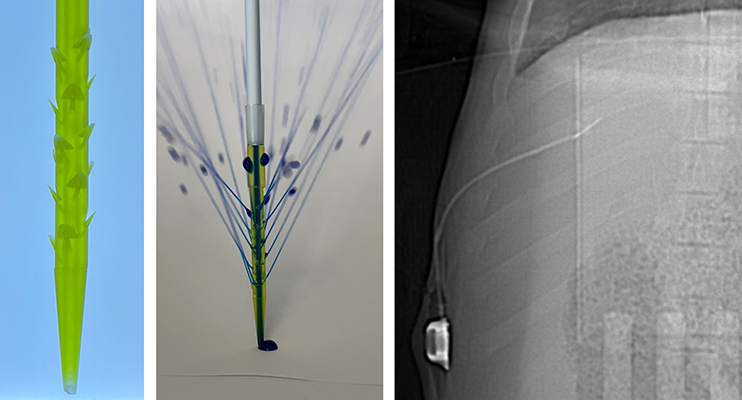

An intratumoral infusion port catheter enables direct infusion of immunotherapy agents into tumors, using arbitrary dosing schedules. The catheter has barbed sideholes, modeled after the barbs in a bee stinger. The barbs maintain the catheter position in the liver tumor, despite respiratory motion. High resistance side holes within the barbs regulate fluid flow, improving uniformity of drug infusion into tumor. 183x improvement in local drug delivery.

11/13/2024: We published our 3D-printed "bee stinger" catheter for directly infusing drugs into tumors. 183x improvement in local drug delivery!